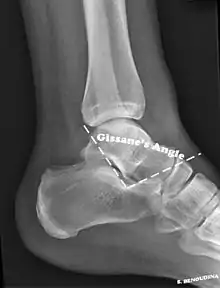

The Angle of Gissane, or "Critical Angle", is the angle formed by the downward and upward slopes of the calcaneal superior surface. On a lateral radiograph, an angle of Gissane > 130° suggests fracture of the posterior subtalar joint surface. Bohler's angle, or the "Tuber Angle", is another normal anatomic landmark seen in lateral radiographs. It is formed by the intersection of 1) a line from the highest point of the posterior articular facet to the highest point of the posterior tuberosity, and 2) a line from the former to the highest point on the anterior articular facet. Bohler's angle is normally 25° to 40°.[13] A decreased angle is indicative of a calcaneal fracture.